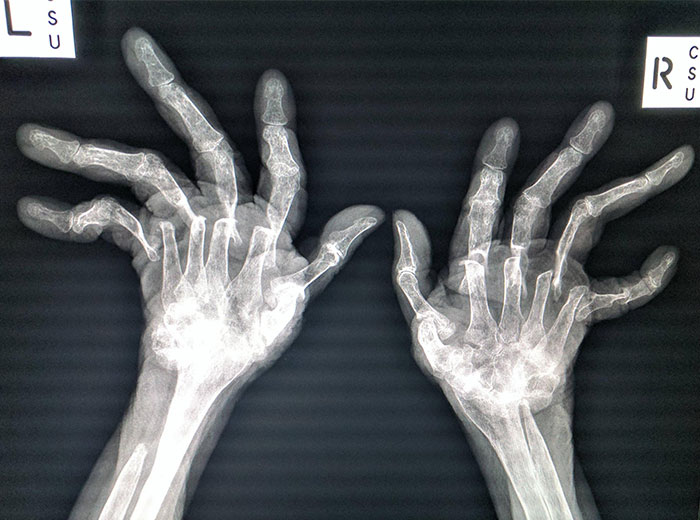

Advanced Rheumatoid Arthritis

My daughter was diagnosed with RA when she was 13. She is 29 now and has had three surgeries to improve her joints to help her be able to walk. Her toes looked much like this X-ray. This is a horrible illness that is invisible until it is at this point. The pain that these patients deal with every day is heartbreaking. People still give her dirty looks when she uses a handicap parking space. Imagine if your toes looked like this...don't you think you would want to walk as little as possible?

The Worst Case Of Rheumatoid Arthritis I've Ever Seen